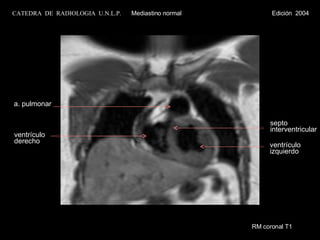

RM coronal T1 ventrículo izquierdo septo  interventric. ventrículo  derecho CATEDRA  DE  RADIOLOGIA  U.N.L.P.   Mediastino normal  Edición  2004

RM coronal T1 ventrículo izquierdo septo  interventricular ventrículo derecho a. pulmonar CATEDRA  DE  RADIOLOGIA  U.N.L.P.   Mediastino normal  Edición  2004